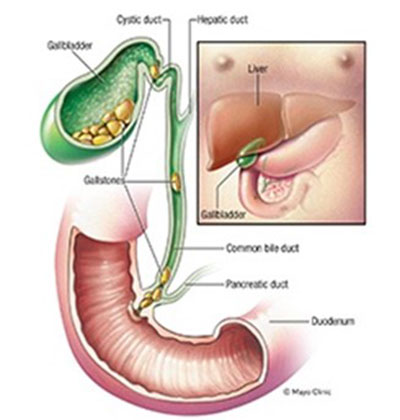

The gallbladder is a small, pear-shaped organ located beneath the liver, where it stores bile, a digestive fluid essential for breaking down fats in the diet. While the gallbladder stores bile, it does not produce it. The liver is responsible for bile production, which flows through the bile duct into the intestine to aid digestion. The gallbladder's function of storing bile was more important in ancient times, when humans had longer gaps between meals. In modern life, where we eat more frequently, this function is no longer necessary, and the gallbladder can be safely removed without impacting digestion.

Around 20% of people develop gallstones, and the risk increases to 30% in individuals who are obese, female, or have a family history of the condition. Gallstones form when the balance of substances in bile, such as cholesterol, bile salts, lecithin, and bilirubin, becomes disrupted. This imbalance causes the bile to become "lithogenic," meaning it forms crystals that eventually develop into stones. Gallstones can range in size from tiny grains of sand to large, golf ball-sized stones. Some people have only one gallstone, while others may develop many.

Additionally, gallstones can migrate into the bile duct, potentially causing jaundice or blocking the pancreatic duct, which can lead to pancreatitis.